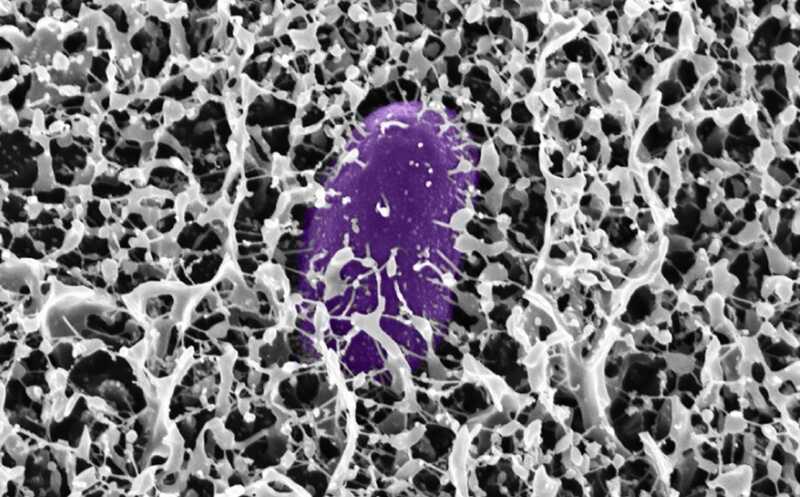

Гликаны кишечной слизи «разоружают» сальмонеллу

Ученые из США выяснили, как слизь, покрывающая кишечник, защищает организм от опасных бактерий, таких как Salmonella enterica серовара Typhimurium. Оказалось, что муцин MUC2, основной гликопротеин слизи, действует не просто как физический барьер, но и как химический агент, который подавляет экспрессию ключевых генов вирулентности сальмонеллы, мешая ей вторгаться в клетки.

Слизь защищает кишечник от бактериальных патогенов. Ключевую роль в этой защите играет гликопротеин муцин MUC2. Он снижает нагрузку бактериальных патогенов и тяжесть кишечных инфекций. Исследователи из США описали механизм, который гликаны муцина используют, чтобы подавить инвазию Salmonella enterica серовара Typhimurium (S. Typhimurium). В частности, они определили, могут ли гликаны подавлять экспрессию островка патогенности SPI-1 (Salmonella Pathogenicity Island 1) — кластера генов, кодирующих систему секреции третьего типа (T3SS). T3SS необходима сальмонелле для проникновения в эпителиальные клетки организма-хозяина.